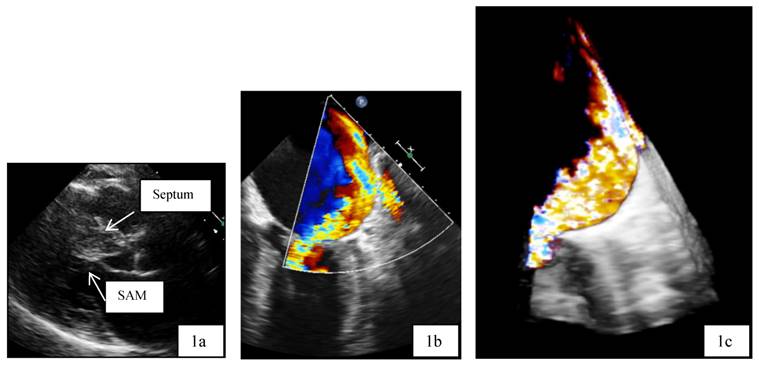

All 4 patients underwent the procedure with the second-generation CB, 28 mm. With the Mapping catheter AchieveTM, we found PV potentials in all veins. After a mean of 2.2 applications, all veins were isolated (e.g. Figure 5). Total procedure time was 140, twice 120 and 100 minutes, respectively. Mean minimal temperatures reached in the LSPV were -49.1±5.4°C, in the LIPV -50.6±11.58°C, in the RSPV -51.3±4.1°C, and - 43.0±6.6°C in the RIPV.

Figure 5

Fluoroscopic view during AF ablation in Right Anterior Oblique view (RAO 30). Pulmonary vein isolation in the left inferior pulmonary vein with the second generation of the cryoballoon technology. The mapping catheter (Achieve catheter) is deep in the pulmonary vein, as the ablation catheter (cryoballon) is attached to the PV-ostium. The coronary sinus catheter is introduced in the coronary sinus for orientation and stimulation purposes.